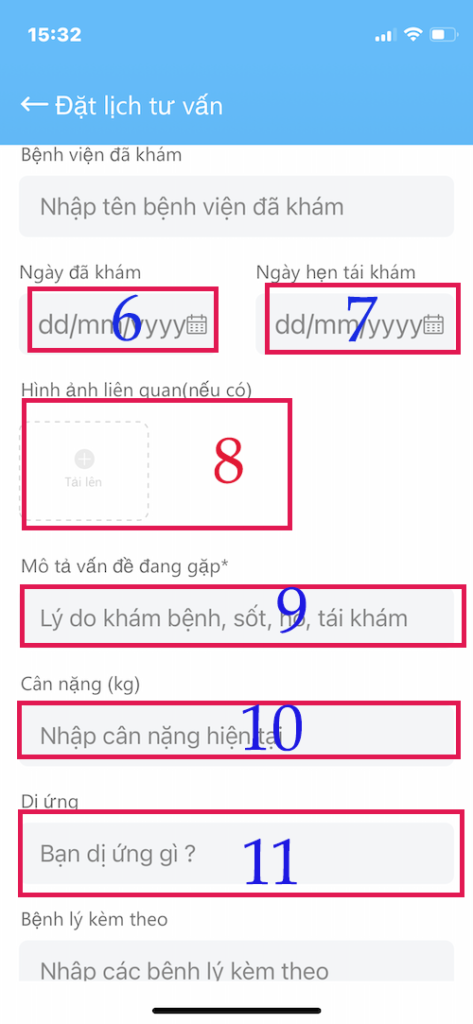

KHAI BÁO THÔNG TIN (tiếp theo)

Quan trọng nhất: trong Khai báo thông tin

- SỐ 8 là quan trọng nhất

- (6) Ngày đã khám trước đó (nếu có)

- ((7) Ngày tái khám theo hẹn (nếu có)

- (8) TẢI HÌNH TOA THUỐC, GIẤY XUẤT VIỆN lên đây hoặc các hình ảnh vết thương, kết quả xét nghiệm,… Cung cấp cho Bác sĩ thông tin rất quan trọng để Bác sĩ điều trị cho Bạn tốt nhất.

- (9) Mô tả triệu chứng của Bạn đang có. Cũng khá quan trọng

- (10) Cân nặng hiện tại

- (11) Tiền căn dị ứng (nếu có)